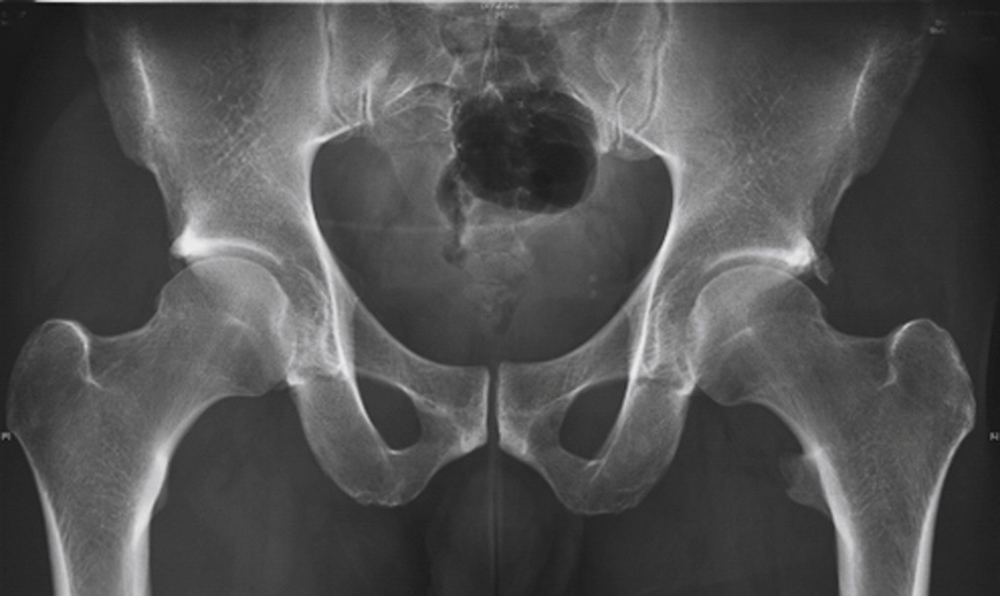

骨の個人差

上記の写真で見てのとおり、ソケットの役割をする寛骨球の位置に大きな個人差があるだけでなく、大腿骨頭の形や角度にも大きな個人差があるために、可動域も可動域の角度も人によってまったく違ってくるのです。